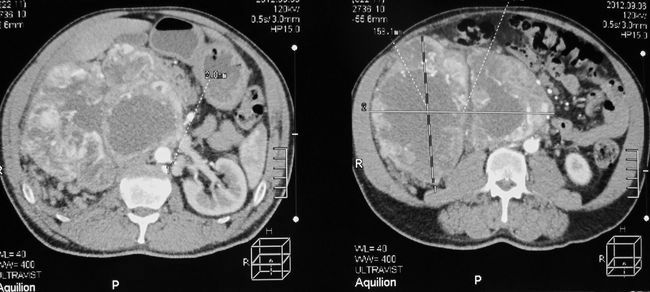

Опухоль правой почки (компьютерная томография)